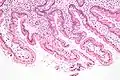

Гистология

Двенадцатиперстная кишка имеет особое гистологическое строение слизистой, делающее её эпителий более устойчивым к агрессивности как желудочной кислоты и пепсина, так и концентрированной жёлчи и панкреатических ферментов, чем эпителий дистальных отделов тонкой кишки. Строение эпителия двенадцатиперстной кишки отличается также и от строения эпителия желудка.

- В подслизистой основе двенадцатиперстной кишки (особенно в верхней её половине) располагаются дуоденальные (Бруннеровы) железы, по строению сходные с пилорическими железами желудка.

Двенадцатиперстная кишка собаки (X100)

Двенадцатиперстная кишка с амилоидными отложениями в собственной пластинке слизистой

Двенадцатиперстная кишка кошки (X60)

Микрофотография, показывающая лямблиоз на дуоденальной биопсии (H&E stain)

Двенадцатиперстная кишка с щеточной каемкой (микроворсинками)